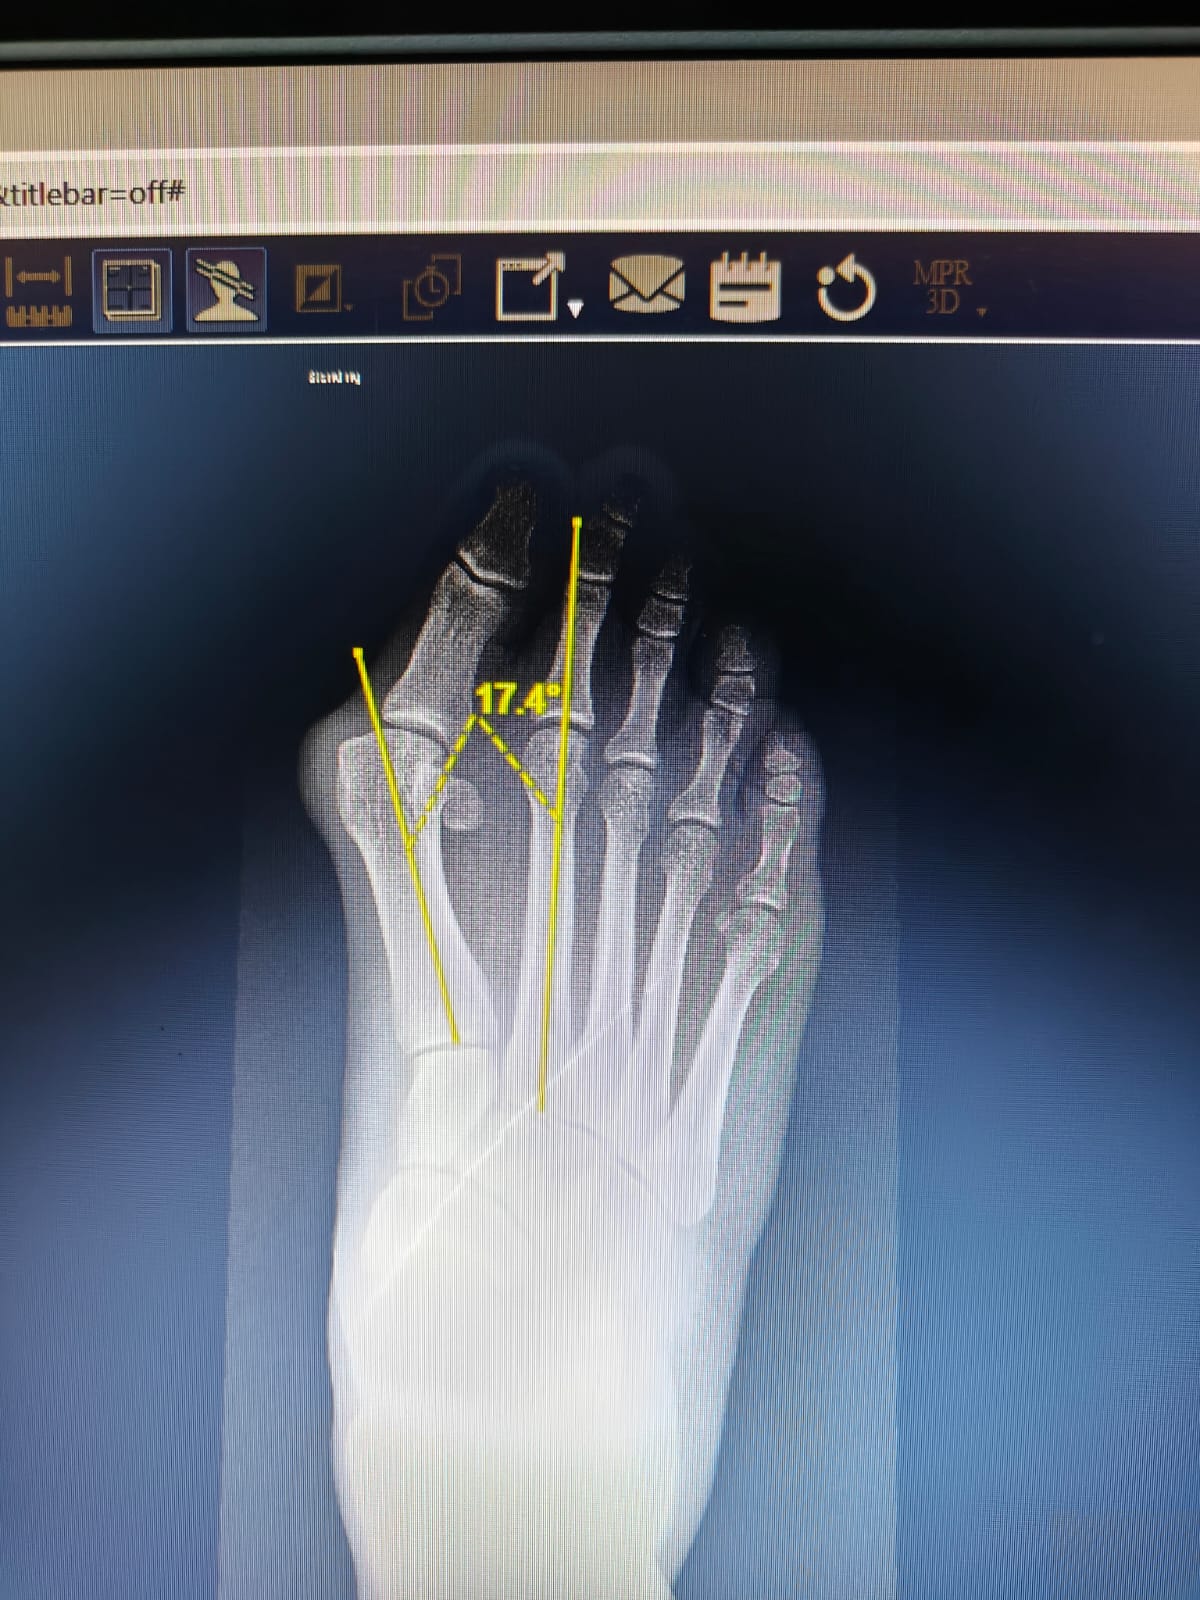

ولفت إلى أن المريض كان يعاني من حالة مرضية تسمى طبياً " إبهام القدم الأروح" وتحدث عندما تتجه قاعدة إصبع القدم الكبير بشكل غير طبيعي إلى الخارج بعيدًا عن القدم ويتَّجه طرف إصبع القدم الكبير نحو الإصبع الثاني، الأمر الذي يسبب عدم القدرة على الوقوف والمشي .

وذكر أنه تم إجراء الجراحة بنجاح عن طريق تعديل المشط الأولي بواسطة تثبيت المفصل الرصغي المشطي الاول بالقدم، بواسطة جروح دقيقة، الأمر الذي يحافظ على الأنسجة المحيطة بالمفاصل والعظام ما يحافظ على التروية الدموية.

وأوضح الدكتور خليفة أن إجراء عملية تثبيت مفصل قاعدة إبهام القدم بواسطة الجروح الدقيقة حققت نجاحاً كبيراً حيث بدأ المريض في العلاج الطبيعي واسترد القدرة على السير باستعمال عكاز بعد التدخل الجراحي بأسبوعين، كما بدأ المريض بارتداء الأحذية بدون معانا